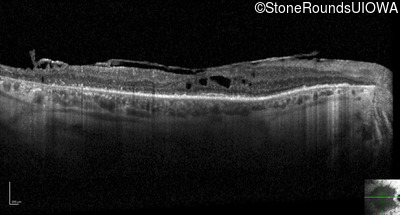

Optical Coherence Tomography - Right - 20/50

Exemplar / OCT Stack

OCT Stack